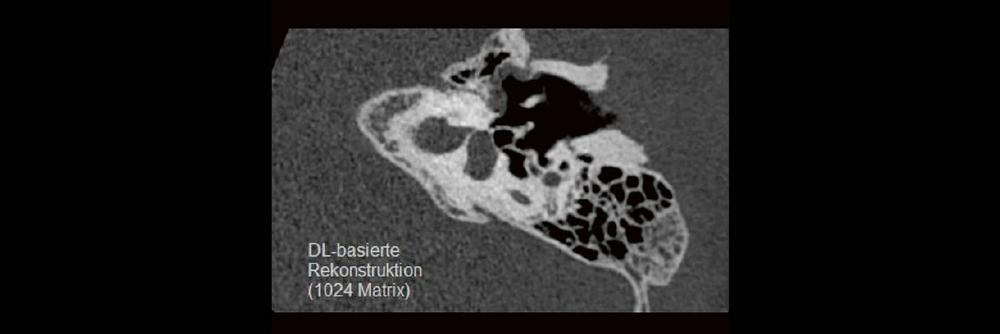

Professor Dr. med. Marc Brockmann WEITERENTWICKLUNGEN VON KOPF BIS FUSS BEIM VC Oberstarzt Dr. med. Stephan Waldeck DEEP-LEARNING-REKONSTRUKTION IN DER NEURORADIOLOGIE Die CT ist ein essentielles Routine-Verfahren in der Neuroradiologie. Bei steigender Bildqualität konnte die Röntgendosis mit neuen Technologien in der letzten Dekade deutlich gesenkt werden, was für die zielgerichtete und möglichst schonende Behandlung von